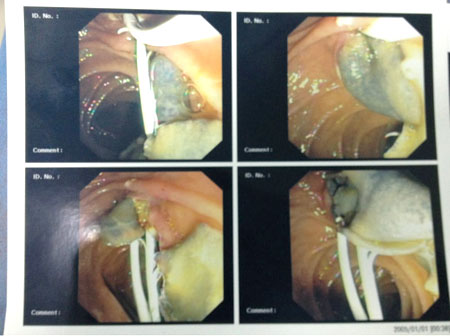

Nội soi mật tụy ngược dòng (ERCP):

Thủ thuật nội soi mật tụy ngược dòng vừa có giá trị phát hiện, chẩn đoán, vừa có giá trị điều trị giải quyết trực tiếp sán kẹt, nhất là khi trong pha mật thì thủ thuật này giúp lấy sán và cầm máu nếu có dấu xuất huyêt đi kèm.